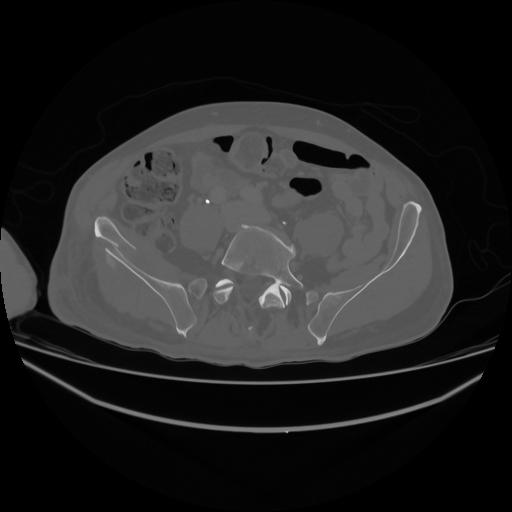

5 CUERPO,CE,Vol,1.0,CUERPO,,